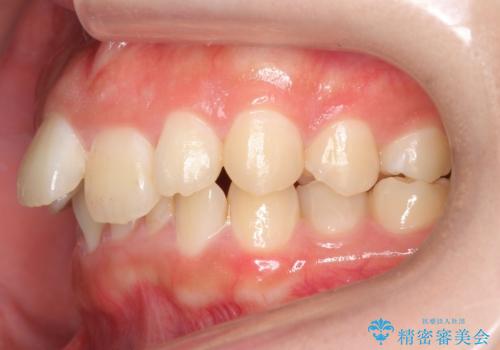

出っ歯をセラミックで治したい

- 前歯の突出を主訴に来院。

矯正治療は絶対したくないとのことでした。

部分矯正なども提示しましたが、早く治すセラミック治療を選択されました。